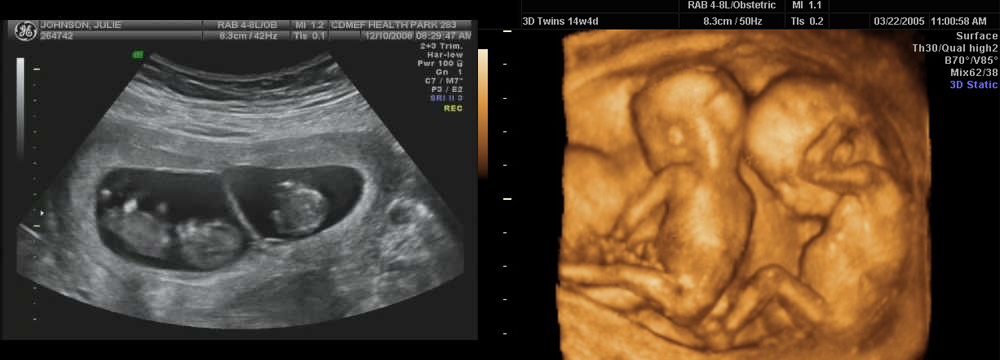

Фотографии на ранних этапах беременности

Раздел: Визуальный дайджест